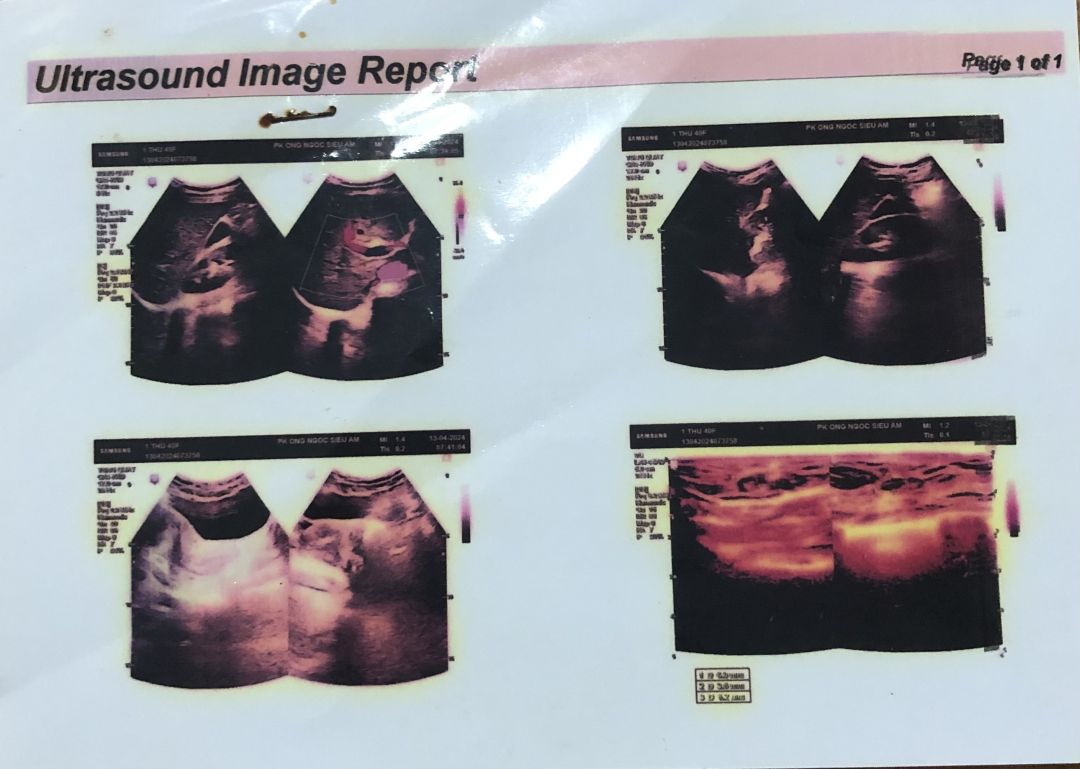

O Hoàng Thị Thư sinh năm ngày 10/2/1984. O bị ung thư vú vào viện mổ ngày 17/10/2025 trong tình trạng khối u đã lan rộng và bị vỡ, O đang trong liệu trình hoá trị nhưng O đã xin ngưng điệu trị vì do sức khoẻ đã quá yếu, bệnh đã di căn (giai đoạn cuối). Hoàn cảnh gia đình đặc biệt khó khăn, không có điều kiện kinh tế, O không có chồng, không có con hiện tại ở nhờ nhà em gái không ai chăm sóc (gia đình em gái cũng khó khăn và đang đi làm xa ở Hà Nội), bản thân O lắng không đủ khả năng lo liệu hậu sự cho mình khi qua đời. Nguyện vọng của O là xin giúp đỡ một áo quan để khi nhắm mắt xuôi tay O được an nghỉ. Sđt O Thư: 0977146168

Chị tên Hoàng Thị Thư. Sn 1984 Chị bị ung thư Vú đã mổ nhưng vì hoàn cảnh gia đình quá khó khăn không có vô thuốc hoá trị. Sau mổ chỉ uống thuốc lá nam nên bệnh tái phát, chị đang ở nhờ nhà em gái ở địa chỉ xóm Xuân đông, Bích hào, Nghệ an. Đt: 0977146168. Hiện tại chị phải vật lộn với những cơn đau ngày một dày hơn.

Vì đau quá nên hôm nay chị đi khám và được bác sĩ thông báo khối u đã di căn nhiều nơi bệnh đã sang giai đoạn cuối. Không có tiền chỉ chỉ lấy thuốc giảm đau rồi ra về trong nước mắt.